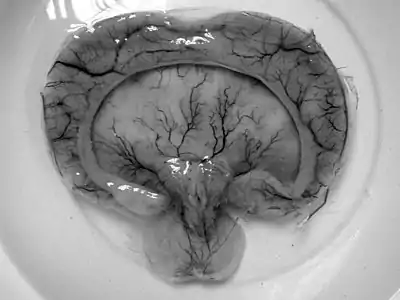

Gross pathology specimen from a case of alobar holoprosencephaly.

- Alobar holoprosencephaly, the most serious form, in which the brain fails to separate, is usually associated with severe facial anomalies, including lack of a nose and the eyes merged to a single median structure (see cyclopia).